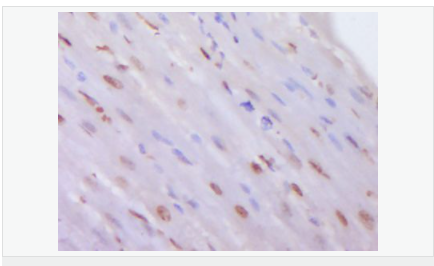

產(chǎn)品應(yīng)用WB=1:500-2000 ELISA=1:5000-10000 IHC-P=1:100-500 IHC-F=1:100-500 Flow-Cyt=0.2μg /Test ICC=1:100-500 IF=1:100-500 (石蠟切片需做抗原修復(fù))